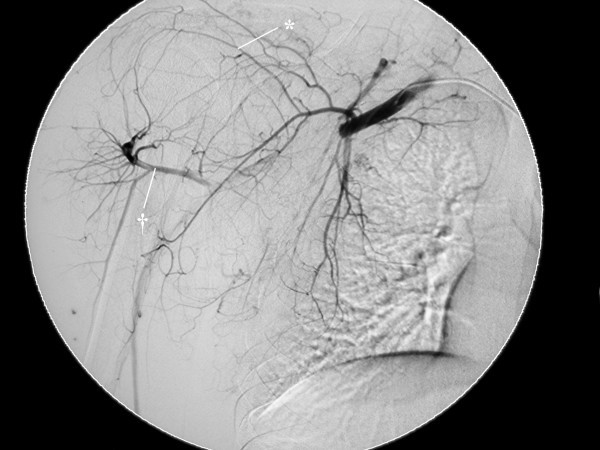

Figure 2

Selective digital subtraction angiography of the axillary artery. The axillary artery was completely occluded at the site of the coracoid process of the scapula, and collateral flow through the thoracoacromial (*) and the posterior circumflex humeral (†) arteries existed.